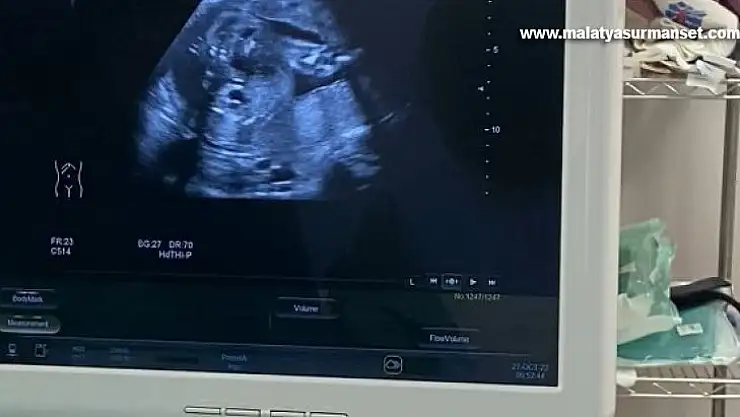

Fethi Sekin Şehir Hastanesi Perinatoloji Polikliniğine müracaat eden gebenin bebeğinde idrar yolu darlığı tespit edildi. Perinatoloji uzmanı tarafından yapılan detaylı muayene ve tetkiklerden sonra anne, bebek sağlığı için bebeğe stent takılması gerektiği belirlendi. Ultrason eşliğinde Vesicoamniyotik Stent takılan bebeğin idrarını yapması sağlandı.

Uygulanan işlemin oldukça hassas olduğunu ifade eden Perinatoloji Uzmanı Dr. Birsen Konukçu Palta, “Vesicoamniyotik Stent uygulması ile bebeğin idrar kesesine takılan bir kanül ile idrarını yapması sağlanır. Bu işlemin amacı bebeğin anne karnında içinde bulunduğu suyun devamlılığını sağlamaktır. Bize başvuran gebemizin bebeğinde idrar yolu darlığı tespit ettik. Öncelikle amniyosentez işlemi ile bebeğin genetiğinin normal olduğunu ve yaptığımız tetkiklerde böbreklerinin hala çalışır vaziyette olduğu belirledik. Şant yapılmasına karar verdiğimiz hastamıza sınırlı bir uyuşturma altında işlemimizi uyguladık. Ultrason eşliğinde yapılan işlem sonucunda bebeğimizin idrarını yapmasını sağladık” dedi.